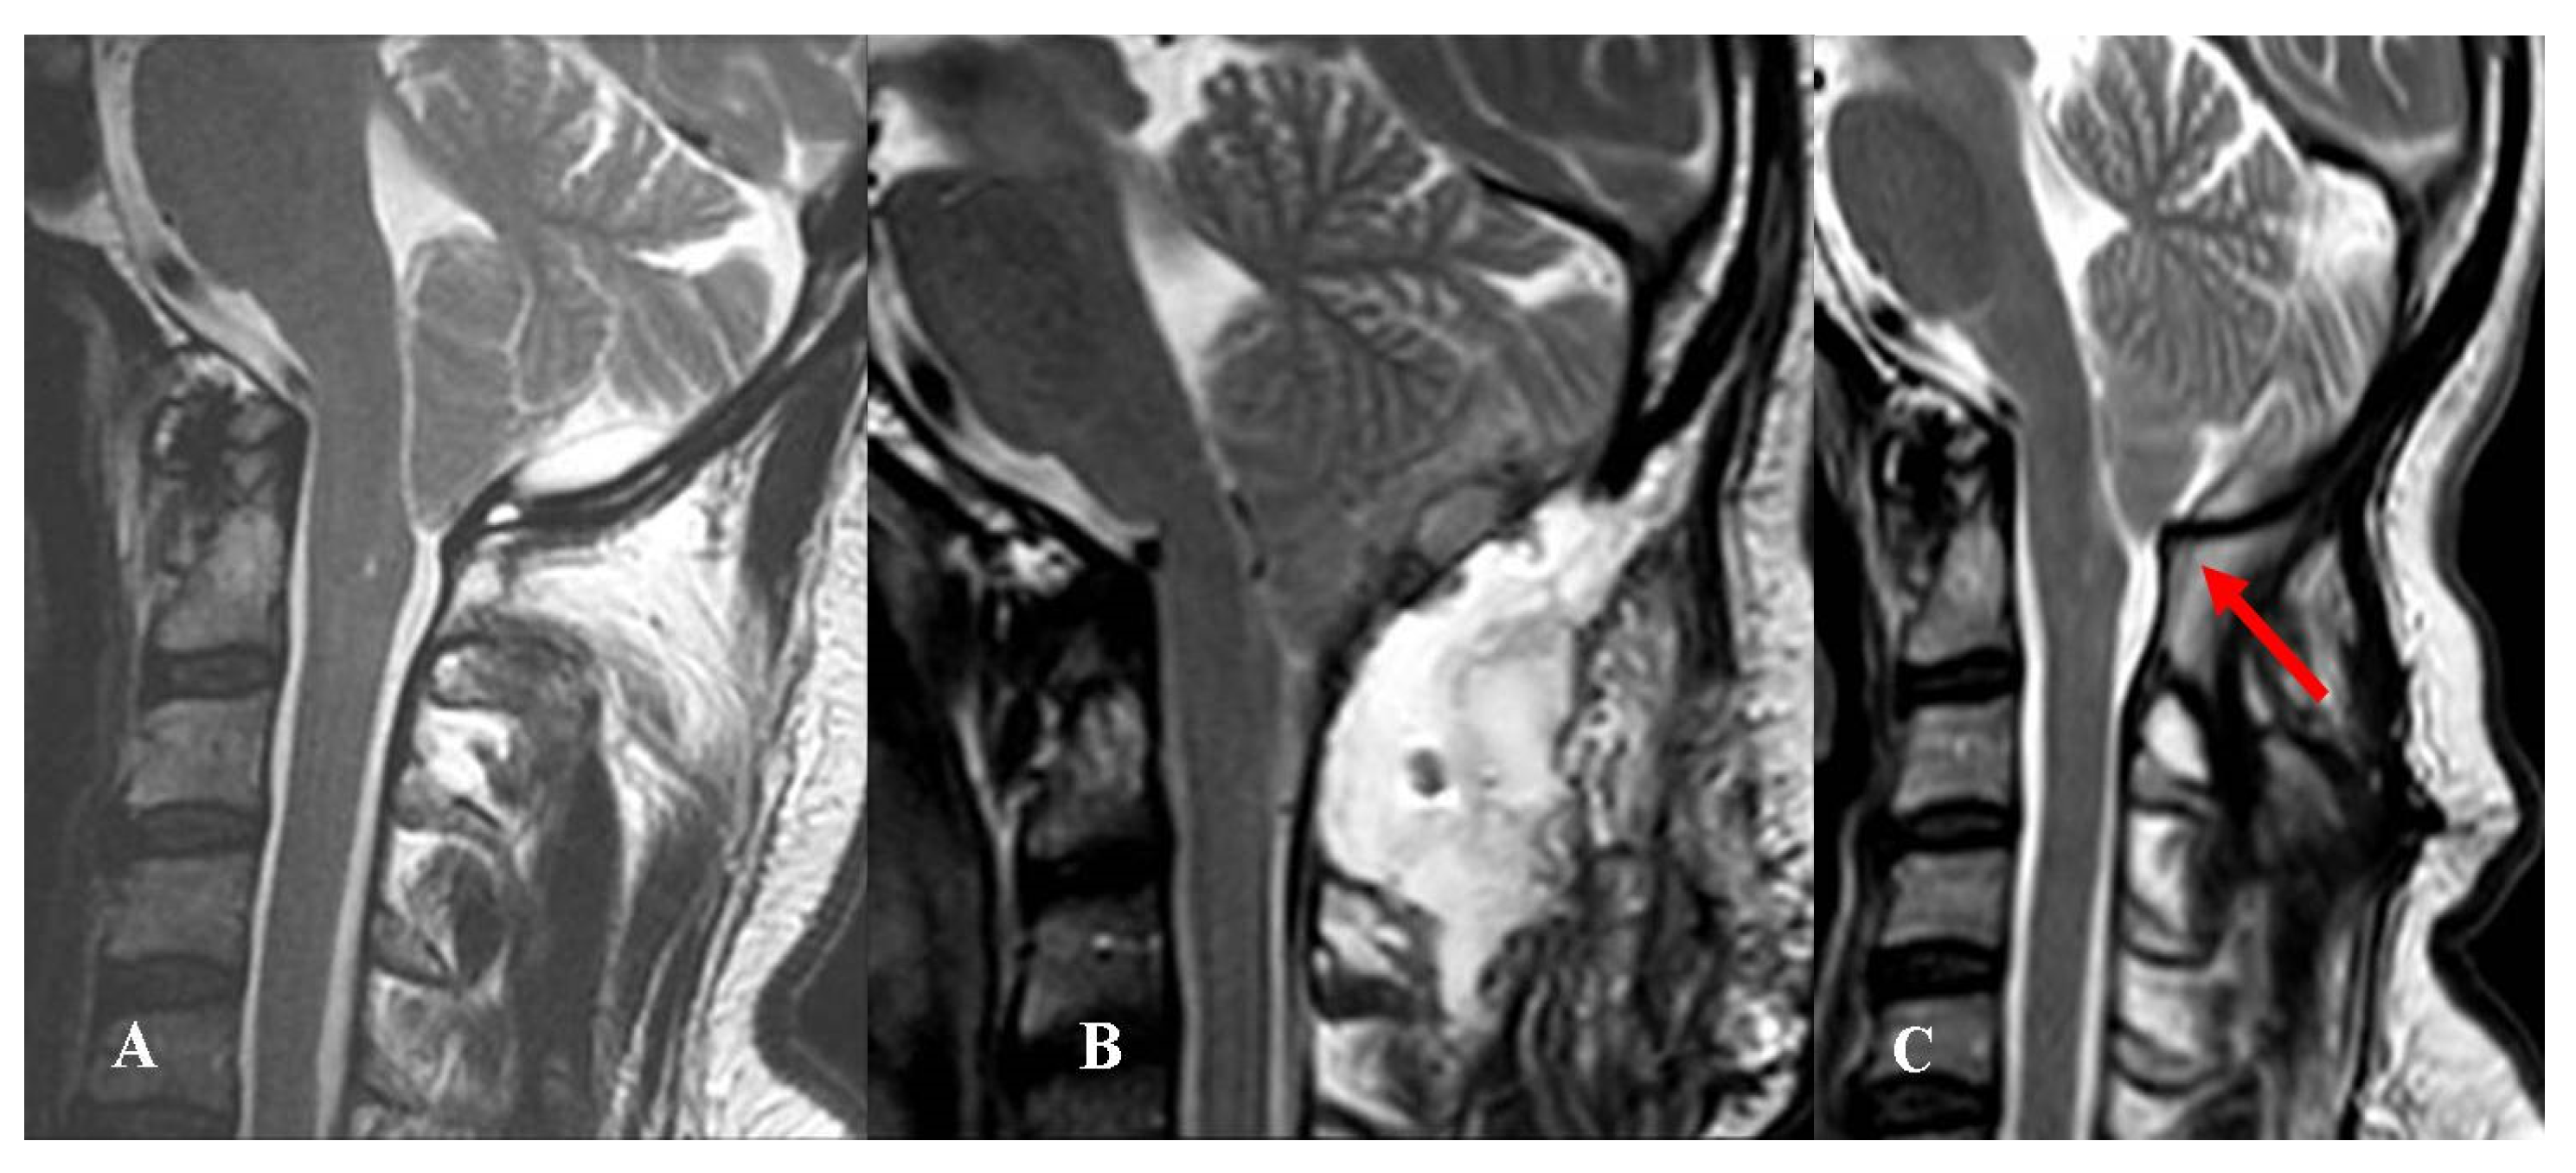

Among the remaining seven patients, two experienced CSF wound leakage and five PSMC with dry skin wound. In four of five cases, the PSMC remained under the muscular layer and no subcutaneous fluid collection was evident (Figure 2).

The two patients with CSF leaks and the one with evident subcutaneous fluid collection underwent revision surgery, whereas the four patients with “internal” PSMC were initially conservatively managed. Since their preoperative headache continued or worsened, they were finally reoperated (7 days to 5 months after the first procedure).

Figure 2. This 48-year-old man complained of an invalidating Valsalva-related headache. (A) Preoperative MRI, T2-weight, sagittal view showing a CM-1.5. Osteodural decompression was performed, and the arachnoid was accidentally violated. The dural sac was repaired using biological graft and fibrin glue. (B) Postoperative MRI, T2-weight, sagittal view showing a deep extradural pseudomeningocele that was not evident at skin level. Conservative treatment was attempted at first. The headache continued to worsen, especially in orthostatism, and 4 months later, he underwent reoperation for duraplasty using autologous fascia lata. (C) Follow-up MRI, T2-weight, sagittal view obtained 9 months after reoperation. There was no evidence of CSF collection; however, the orthostatic pain improved, but the headache did not yet resolve. Adhesions may have developed between the autologous graft and the cerebellum (red arrow). A further surgical procedure was offered, but was refused by the patient. The final CCOS score was 12.